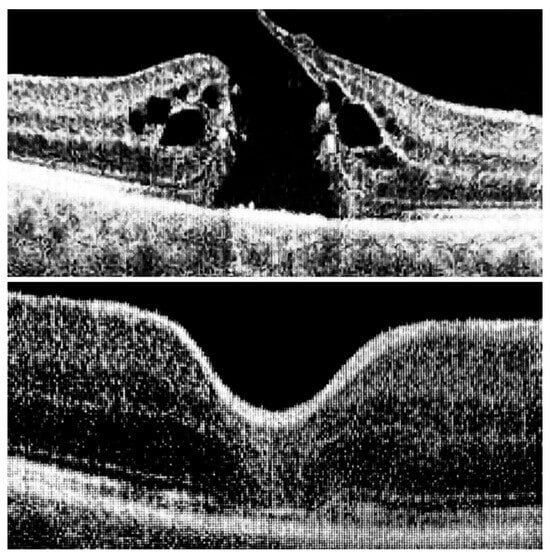

Figure 3. At the top: long-standing macular hole persisting for 12 months; at the bottom: complete closure with restoration of all retinal layers, preserving ideal architecture and morphology, including the ninth layer—the retinal pigment epithelium (RPE).